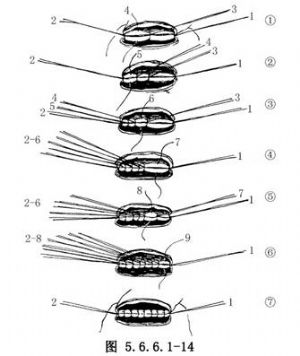

(4)常规食管胃端侧吻合:①先在预计切断食管的平面上方1cm处由食管边缘两侧分别用丝线穿过肌层与黏膜下层,与胃底部预计切开处的浆肌层缝合,两针之间的距离为食管的宽度(图5.6.6.1-10),图中食管壁上的虚线为准备切断食管的平面;②在两根缝线之间加缝数针,将食管后壁与胃底部浆肌层完全缝合(图5.6.6.1-11),图中胃壁上虚线为准备切开胃壁的部位;③切开胃壁浆肌层,但勿切透黏膜,将循行于黏膜下的每根血管用细丝线缝扎两处,然后在缝扎线之间切开胃黏膜。黏膜上切口开始不宜太大,在吻合过程中如嫌不足可再次切开(图5.6.6.1-12)。在切开胃壁之前应先用干纱垫置于吻合口后方以吸取切开胃黏膜后逸出的胃液,切开胃黏膜后迅速将吸引器头送入胃中吸净胃液;④沿预计切断食管的平面环绕食管切开肌层但勿切开黏膜,在食管肌层断面远侧约0.8cm的平面剪断食管黏膜,因留有足够的黏膜,吻合时十分便利,否则如在同一平面切断食管肌层及黏膜,由于后者的回缩使吻合操作相当困难;⑤将吻合口后壁食管全层的左右侧两角分别与胃壁切口的上缘全层用细丝线间断缝合,注意食管黏膜与胃黏膜必须对齐,缝线之间的间隔约为0.4cm,缝线结扎不能太紧以免术后局部组织水肿造成切割,成为发生吻合口瘘的主要因素(图5.6.6.1-13)。结扎线结打在腔内(图5.6.6.1-14);⑥将胃管经吻合口送入胃中,如果应用十二指肠饲食管,可在此时将引导饲食管的糖球一并送入胃中(图5.6.6.1-15),开始吻合前壁。由后壁转往前壁时,两侧转角处的缝线必须缝好,因在转角处容易发生瘘。吻合的最后4~5针最好先挂上线而不结扎,待全部缝合完毕时一次打结;⑦前壁第一层吻合完成以后,撤除原来置于吻合口后方的干纱布块,参加手术人员用无菌净水冲洗手套,将吻合使用过的器械前端用水洗净,用细丝线间断缝合吻合口前壁第二层,完成食管肌层及黏膜下层与胃底部浆肌层之间的缝合(图5.6.6.1-16);⑧将吻合口周围的胃壁用纱布向吻合口方向推送,结扎吻合口前壁第二层的缝线,使吻合口最后被套入胃壁中(图5.6.6.1-17);⑨将胃内引导十二指肠饲食管的糖球挤过幽门,清点台上敷料(包括纱布及纱垫)无误后,用中号丝线间断缝合膈肌。在胃越过膈肌处缝合不宜过紧,防止术后出现梗阻。将胃轻轻上推然后将胃壁与周围膈肌缝合6~7针,防止腹腔内脏器循此途径进入胸腔。注意不要用丝线将胃壁固定在胸壁上,此种缝线可能造成胃壁穿孔。如术者想采取措施减少吻合口的张力,可在近胃底部的胃大弯侧寻找一个切断大网膜的残结,用缝线穿过固定在纵隔胸膜上,同样可以达到吻合口减张的目的而无胃壁穿孔之虞。由第8肋间腋后线置入闭式引流管,检查胸内有无出血点或异物存留。用肋骨合并器将切口上下方的肋骨合拢,肋间组织用中号丝线缝合,冲洗胸壁肌肉,逐层关胸。将闭式引流管连接于水封瓶上。